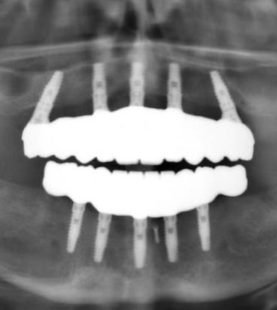

The aim of this live surgery course is to look deeply and carefully at the procedures, skills, and techniques required to provide excellent predictable aesthetic dental implant surgery. In this residency, delegates will have the opportunity to dig further into the techniques and skills required to provide excellent implant surgery, watching and performing their own live surgeries! Various techniques will be investigated, including discussions around modern techniques such as immediate implant dentistry, grafting techniques, live surgery performed by Dr. Dagher, guided surgery protocols and guidance on how to position a collaborative approach with your team to present implant treatment options to more patients.

The Advanced Implant Residency will focus on 4 main topics: Grafting, Sinus lift, Immediate loading and Bone grafting. There will be ample room for full discussion related to all of the above together with the opportunity to review cases of your own patients with Dr. Dagher and perform them under his supervision on site. This ongoing residency will be offered yearly at the Dagher Institute for Advanced Learning. This will provide delegates with a much deeper understanding of aesthetic implant surgery including ongoing support and mentorship from Dr. Dagher. Straumann is proud to collaborate with Dr. Dagher in Hawkesbury to bring you the most comprehensive and advance learning institute in the area.